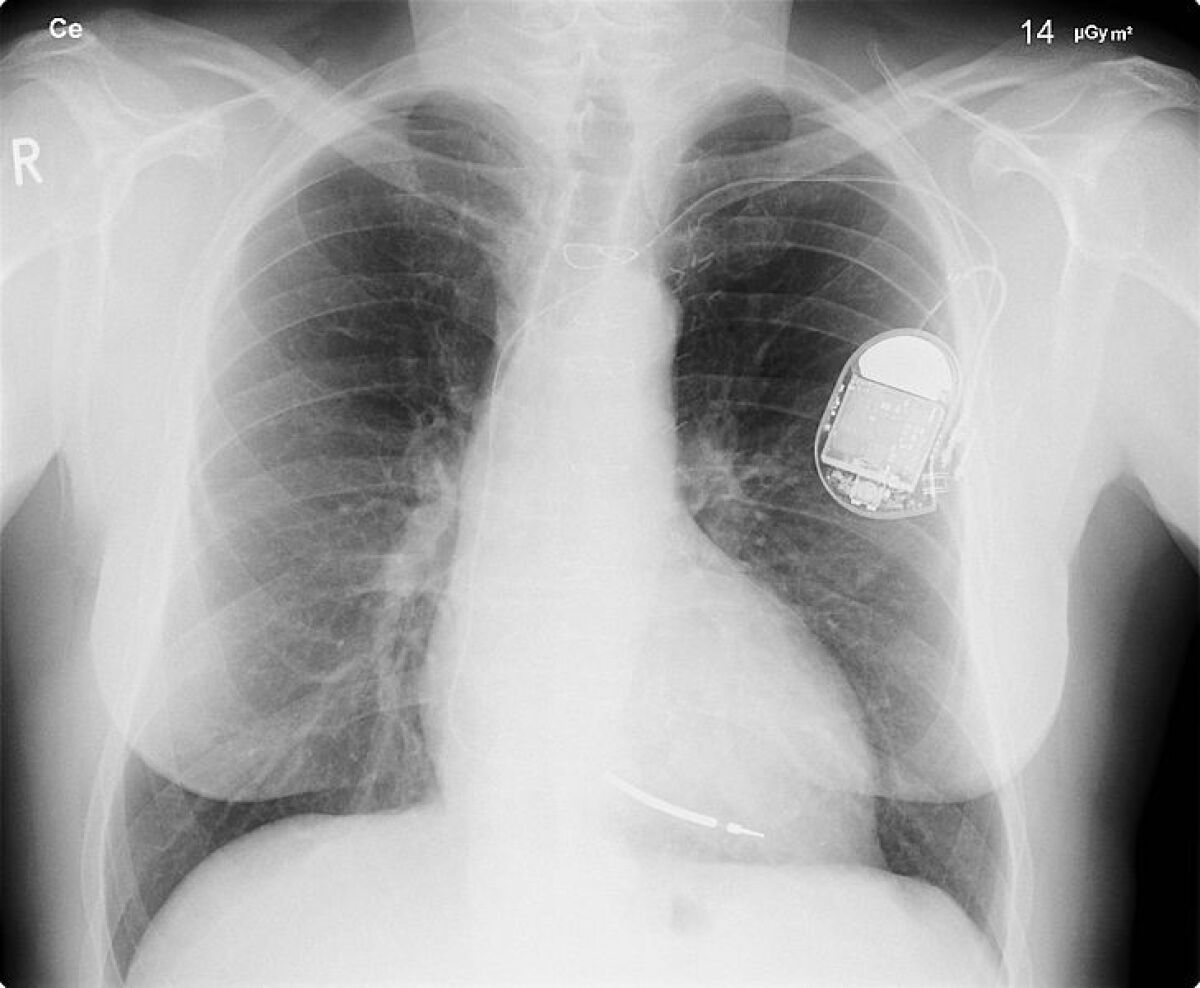

Defibrillator Device Implanted . An icd can help the heart maintain a steady, stable rhythm. — what is an implantable cardioverter defibrillator? Learn who needs them, how are. — an implantable cardioverter defibrillator (icd) is a small device that your doctor can put into your chest to help regulate an irregular heart rhythm, or an arrhythmia. sie sind nur wenige zentimeter groß, können aber leben retten: an implantable cardioverter defibrillator (icd) is a medical device that monitors your heart and manages heart rate when needed. — what is an implantable cardioverter defibrillator? implantable cardioverter defibrillators (icds) are small devices to treat abnormal heart rhythms.